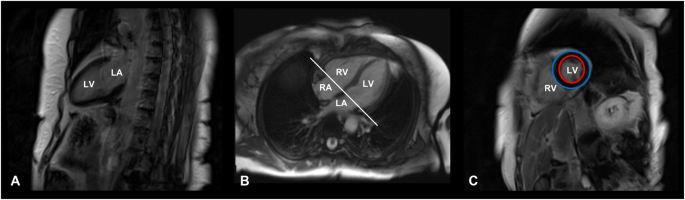

The main steps of CMR image acquisition are shown in Fig. 1.

Cardiac magnetic resonance image acquisition protocol. T1-weighted, late gadolinium enhancement cardiac MR images of a 71-year-old female patient with Cushing’s disease, cured after successful neurosurgery. A Vertical long axis slice, coronal plane, two-chamber view. B Horizontal long axis slice, axial plane, four-chamber view. C Short-axis slice at the end of the diastole, sagittal plane. Red circle: endocardium; Blue circle: epicardium. LA left atrium, LV left ventricle, RA right atrium, RV right ventricle